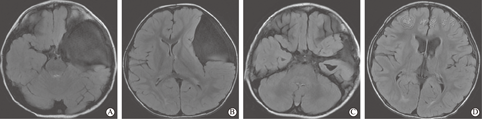

病理标本114例:110例为蛛网膜囊肿、4例为室管膜囊肿。所有病例得到随访,随访时间为术后3个月~7年,平均(13.7±11.4)个月。术前有临床症状者,术后不同程度好转,其中语言发育明显好转,2例术后仍有癫痫发作,但频率减少。Ⅲ型囊肿术前和术后1年头颅MRI对比见图1。术后囊肿分型与转归的关系见表1。囊肿消失的患儿随访(10.3±5.1)个月,缩小≥1/2的随访(21.4±14.6)个月,缩小<1/2的随访(26.7±26)个月,治愈率72.2%(117/162),优良率89.5%(145/162),有效率96.9%(157/162)。5例无变化及积液加重者中4例有慢性颅高压征,其中2例CT脑池造影显示瘘口关闭,分别再次手术,2例硬膜下积液加重者行硬膜下-腹腔分流术,1例继续观察。术后主要并发症:1例出现不完全动眼神经麻痹,于2个月后完全恢复;65例出现硬膜下积液,转归见表2;2例积液渐加重具有慢性颅高压征(手术年龄均小于1岁);7例出现硬膜下慢性血肿行血肿外引流术。

对于囊壁的剥离度是涉及到手术疗效的焦点,过度剥离产生损伤也直接影响愈后。目前多数学者赞同不要求全剥囊壁只要能达到与脑池和蛛网膜下腔充分沟通[6]、术中尽可能减少出血。对于中颅窝底囊肿,内侧中线部位为鞍上池,对此内镜在锁孔技术、液态环境、多角度和深入浅出的手术操作环境下[14]具备优势。本组均采用内镜直视下对鞍上池进行造瘘和开窗,未主动剥离脑表面蛛网膜,术后随访结果显示疗效满意,72.2%患儿在平均10个月达到囊肿消失(图2:术前、术后1年),且89.5%缩小一半以上(其中Ⅱ型为90.8%、Ⅲ型为87.5%)。内镜手术中无开颅术需排尽囊液所造成颅低压之虑,持续平衡液灌流保持颅压相对稳定和视野的清晰。本组患儿囊肿Ⅰ~Ⅲ型,故因颞叶推移程度不一,内镜进入囊内有三种途径,以使进入囊后能直接正对观察到鞍上池。所有患儿鞍上池呈膜状封闭(图2A),根据鞍上池显露血管神经间隙程度选择视神经前后间隙、颈内动脉-动眼神经间隙、动眼神经后间隙进行膜上开窗,用微型剪刀和球囊扩张相结合最大程度将血管神经间隙打开(图2B),电凝收缩飘动囊壁和窗缘。动眼神经-脑干间存在间脑膜者需继续分离和打开(图2C),直至各间隙内清晰见同侧甚至对侧视神经及颈内动脉各分支、动眼神经及基底动脉、脑干等结构。术中如见中颅窝底囊壁随颅压下降和水流冲击后漂浮者需将之切除,以防止出血和飘落囊壁封堵造瘘口(图2D),如囊壁无松动则不主动强求剥离。囊肿破裂者可见壁层塌陷呈不同程度纤维变、增厚及含铁血黄素沉着,可大部分去除。术中开窗时需精细操作和及时球囊压迫出血点,所有病例未出现不可控的出血。4例囊壁病理为室管膜囊肿,分析其影像与蛛网膜囊肿无异,术中发现囊壁较蛛网膜囊肿厚、韧,囊壁上血管分支较多,术中较易出血,操作上尽量避免牵扯。1例患儿囊压极高见动眼神经压至后岩床上,囊壁韧,打开囊壁见动眼神经周围纤维网状粘连,予分离时存在损伤,术后有动眼神经麻痹症状,但2个月后眼裂和眼球恢复正常。